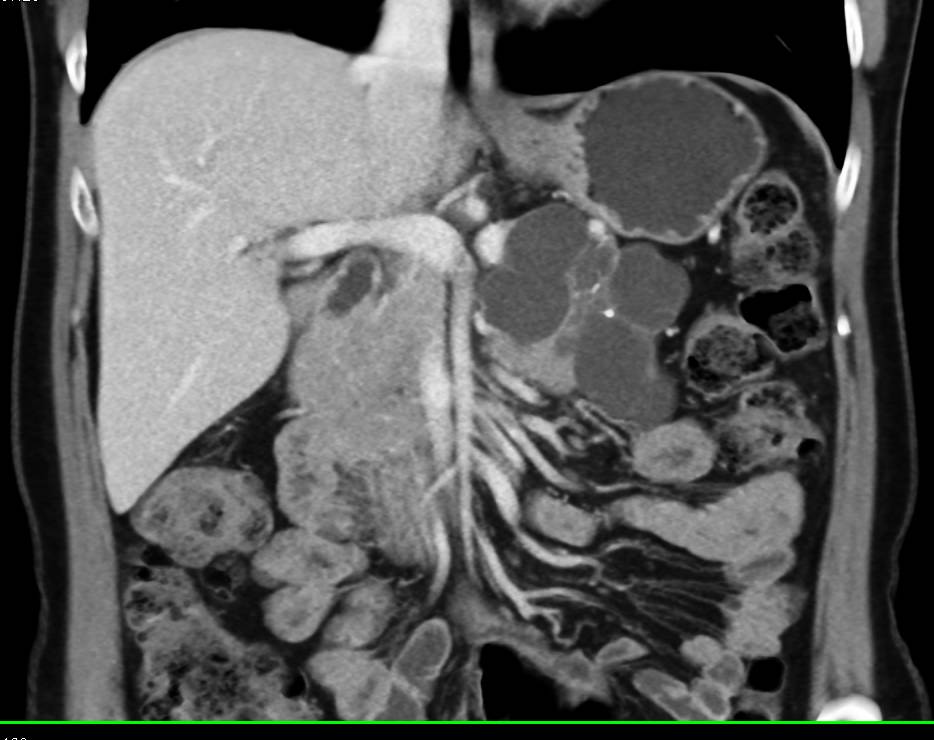

Pancreatic Necrosis with Pancreatic Abscess